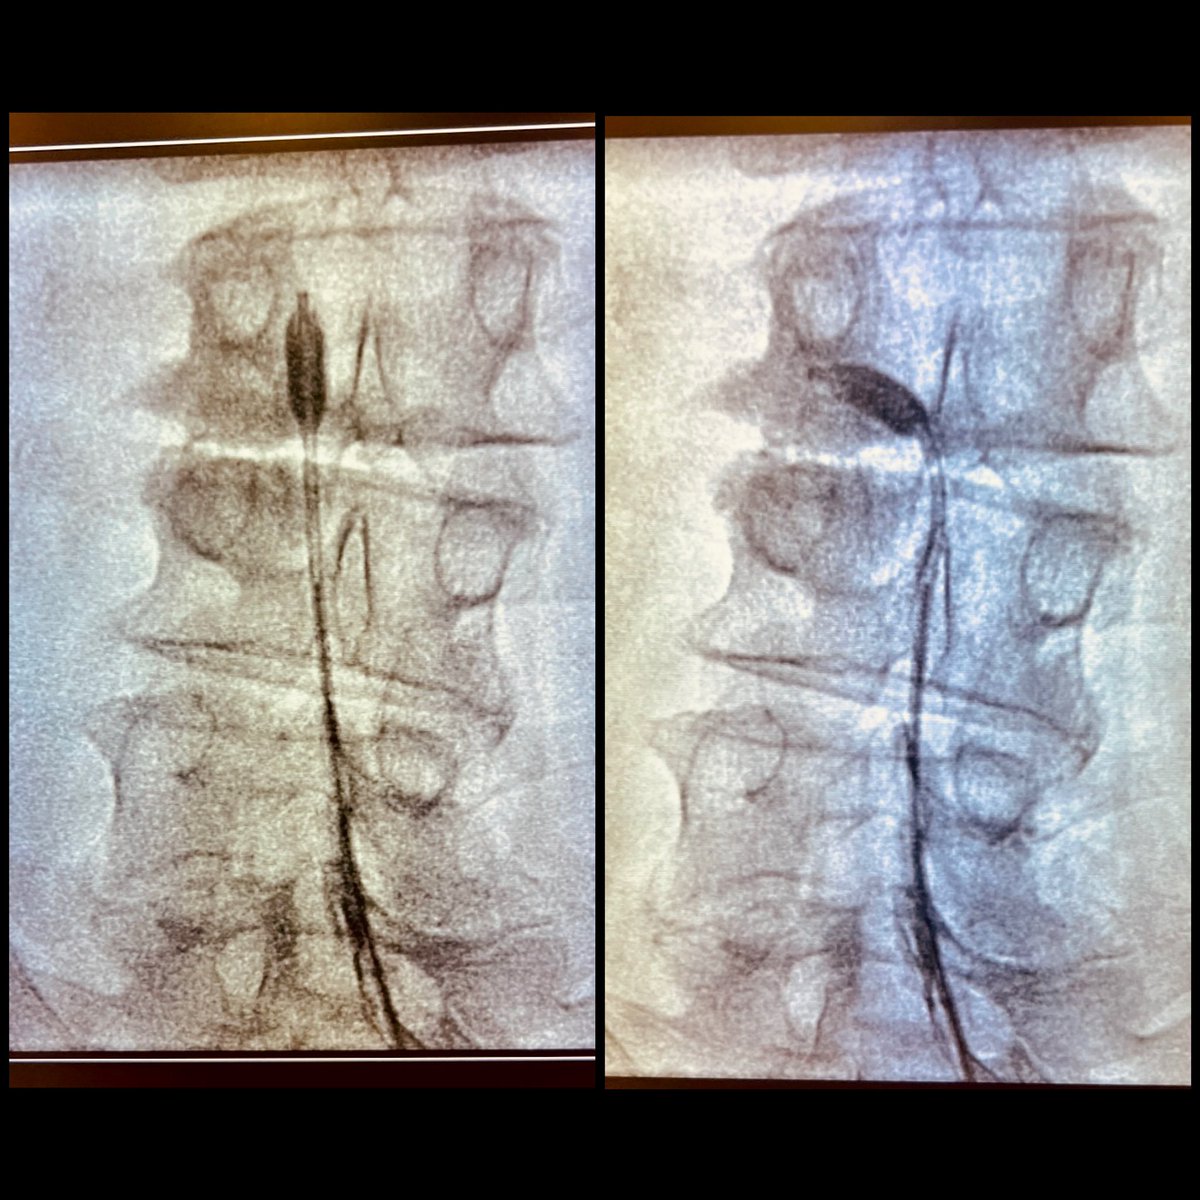

🔵Epidural balloon neuroplasty🔵 Lumbar spinal stenosis in whom epidural block or neuroplasty achieved short-lived effects ✅ Accurate balloon at the target. ✅ Ballooning more than 50% target. ✅ Complete contrast dye spread. quirónsalud Bizkaia Vitoria #painrelief #pain

🔵Epidural balloon neuroplasty🔵

Lumbar spinal stenosis in whom epidural block or neuroplasty achieved short-lived effects

✅ Accurate balloon at the target.

✅ Ballooning more than 50% target.

✅ Complete contrast dye spread.